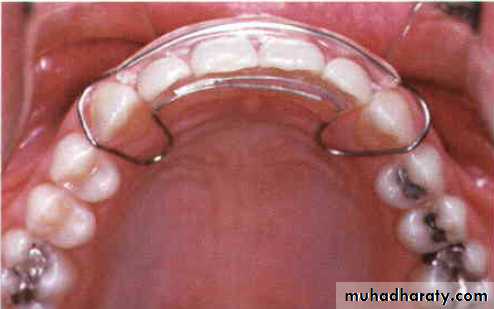

67

A, Closure of a midline diastema can be accomplished with a removable appliance and finger springs to tip the teeth mesially.